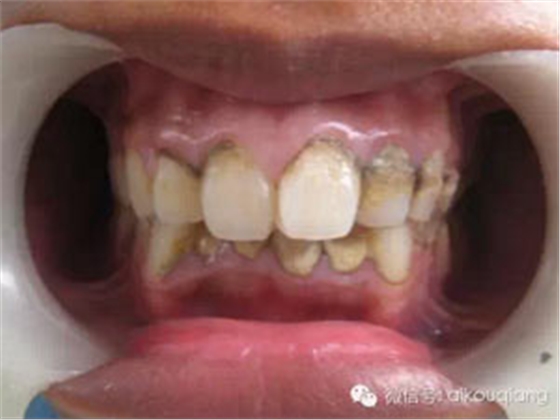

一個(gè)高職學(xué)校的學(xué)生,口腔內(nèi)嚴(yán)重的牙結(jié)石,可能小時(shí)候沒有刷過牙

洗牙(潔治)后效果很明顯